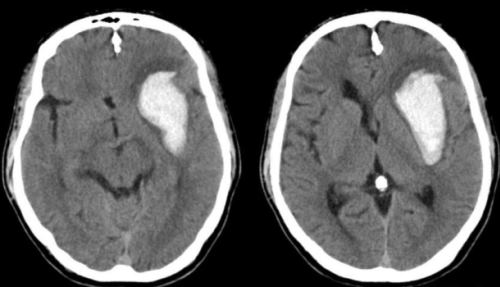

Для диагностики гематом необходимо пройти ряд медицинских анализов и обследований, в частности, КТ и МРТ. Эти методы дают полную картину о состоянии гематомы, ее местонахождении, размерах и способствуют определению патологических процессов, которые уже начали происходить в организме из-за того, что новообразование сдавливает мягкие ткани мозга.

Внутримозговая гематома на КТ.